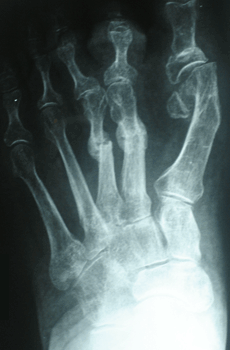

RESULTADOS

Caso 1: Hallux Valgus del Adulto